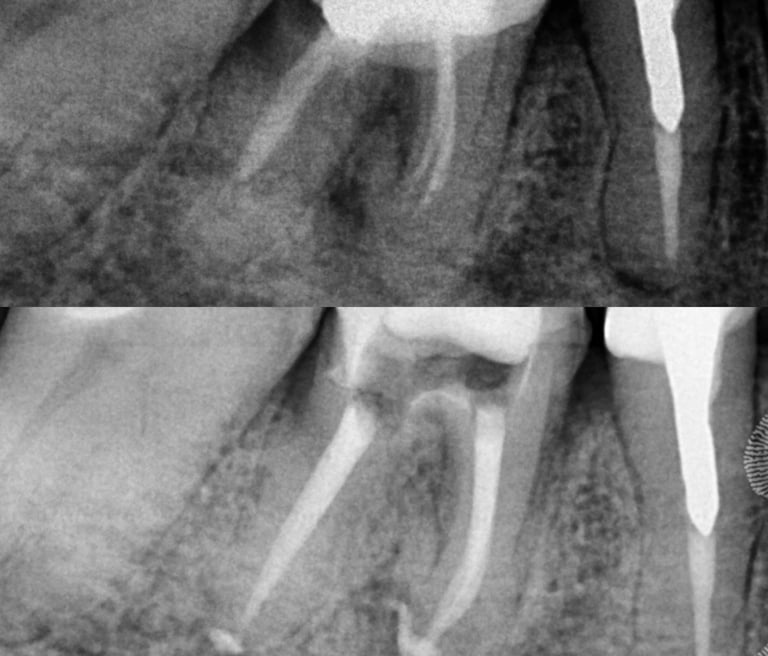

Em alguns casos, a necessidade de tratamento de canal é identificada em exames radiográficos, mesmo antes de o paciente sentir dor.

As radiografias periódicas podem revelar lesões na ponta da raiz, indicando um foco de infecção que precisa ser tratado.

Nesses casos, apenas o tratamento endodôntico é capaz de eliminar o problema e restaurar a saúde do dente.

Galeria

Na odontologia, cada sorriso é único e o resultado final depende de fatores biológicos individuais. Imagens clínicas não constituem promessa de resultado. Planejamento técnico e diagnóstico são fundamentais para o sucesso do tratamento."